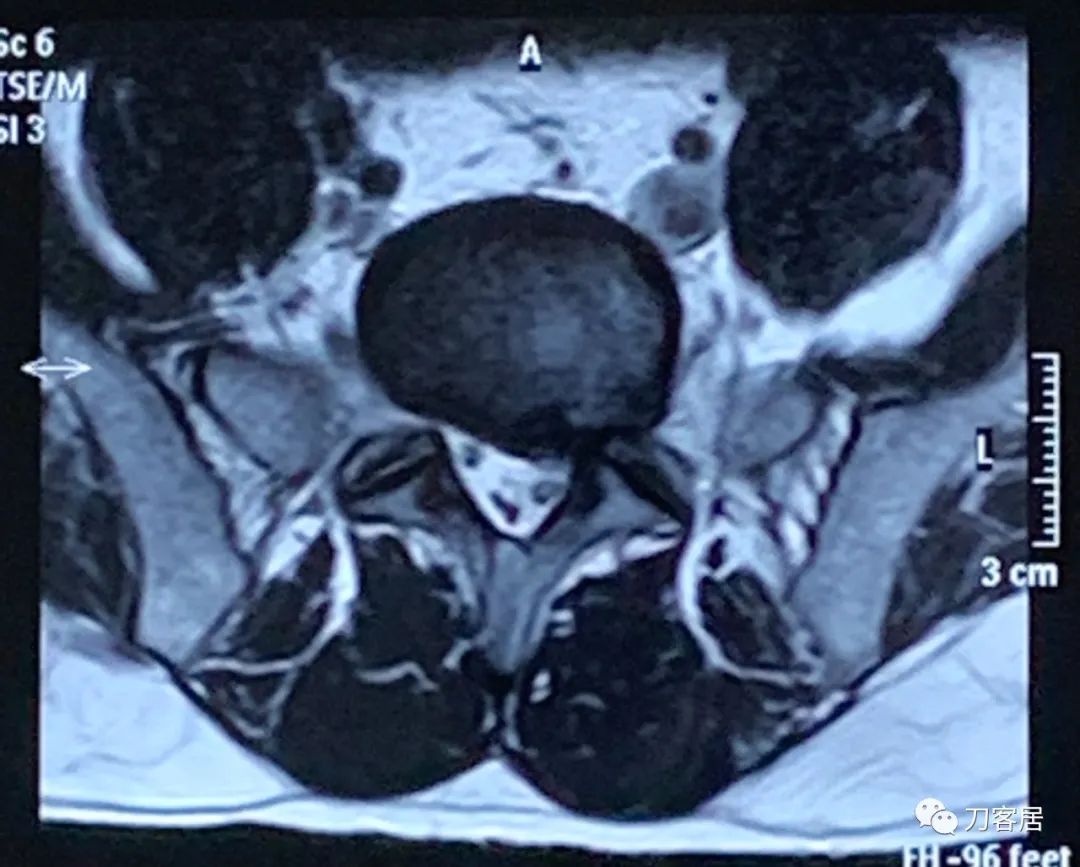

图5. 20220118宁夏医科大学总医院腰椎MRI02,横截面扫描提示腰5骶1椎间盘突出,左旁侧型。

图6. 20220118宁夏医科大学总医院腰椎MRI03,横截面扫描提示腰5骶1椎间盘突出,左旁侧型。